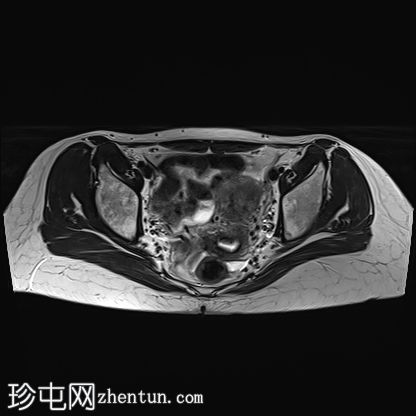

3.jpg

轴位

T2加权像

左侧股骨头:

T1和T2加权像上可见股骨头前上缘呈蛇形低信号,勾勒出一个地理区域,STIR序列上可见邻近骨髓水肿。

软骨下骨折/新月征,关节面局灶性凹陷——符合软骨下塌陷。

关节间隙中央保持完整,但股骨头轮廓异常,系塌陷所致。

关节周围结构:无大量关节积液,无骨关节炎性关节间隙狭窄或边缘骨赘,提示无晚期继发性退行性改变

未发现其他部位急性骨折